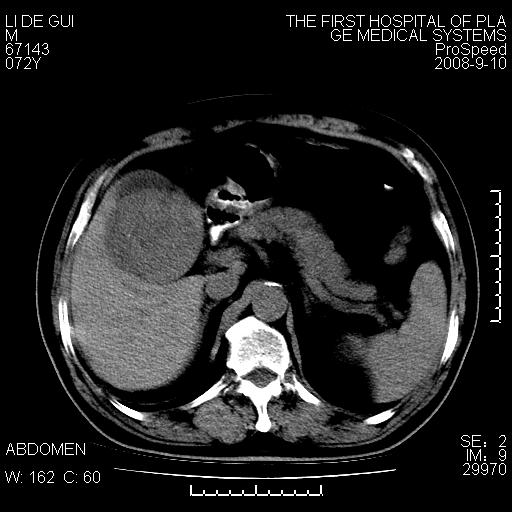

标题: CT17988:腹部肿块两年,肿块大小无变化,患者无不适,自我 [打印本页]

标题: CT17988:腹部肿块两年,肿块大小无变化,患者无不适,自我

不可思议!两年无变化无症状?建议详查!

胆囊占位性病变(黄色肉芽肿性胆囊炎?)。

考虑-----胆囊血肿机化或胆囊癌或腺肌增生症------增强

十二指肠的间质瘤